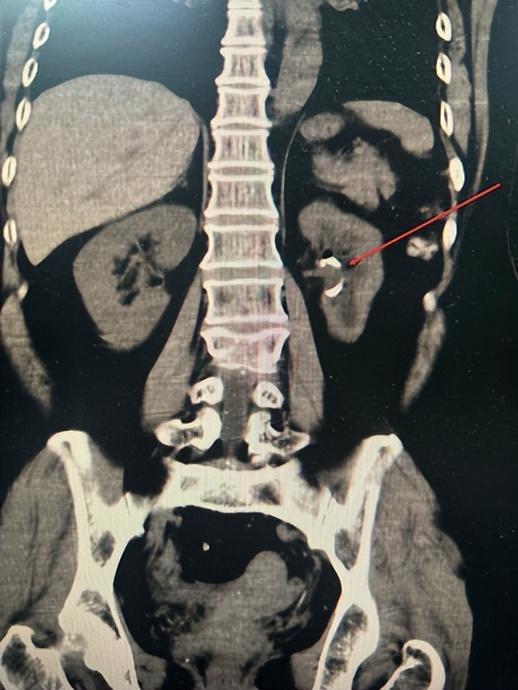

医生为其完善检查后,发现不是结石,而是肾脏重度积水,结合患者病史及辅助检查,被确诊为输尿管狭窄合并重度肾积水。完善输尿管镜检,并予以扩张、输尿管支架置入后,肾积水基本消失,但患侧肾脏功能已受到明显损伤。

(▲肾积水基本消失)